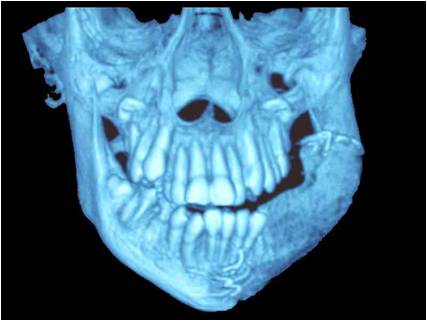

Дете с тумор на долната челюст. Лечението налага нейната резекция. Възстановена е едномоментно чрез микросъдова реконструкция с част от тазова кост. Първата успешна микросъдова долночелюстна реконструкция в България – случай на доц. Джоров.